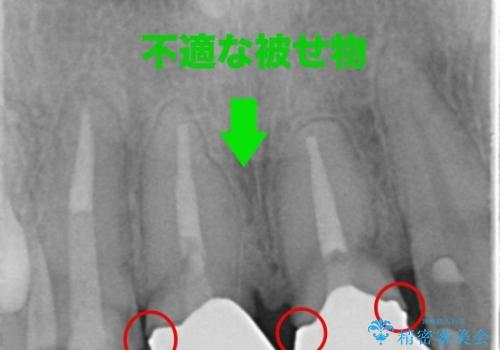

レントゲンを撮ったところ前歯の被せ物が不適でした。

根管治療はご希望されなかったので(症状はなし)被せ物のやりかえ、右上2は被せ物の治療を行いました。